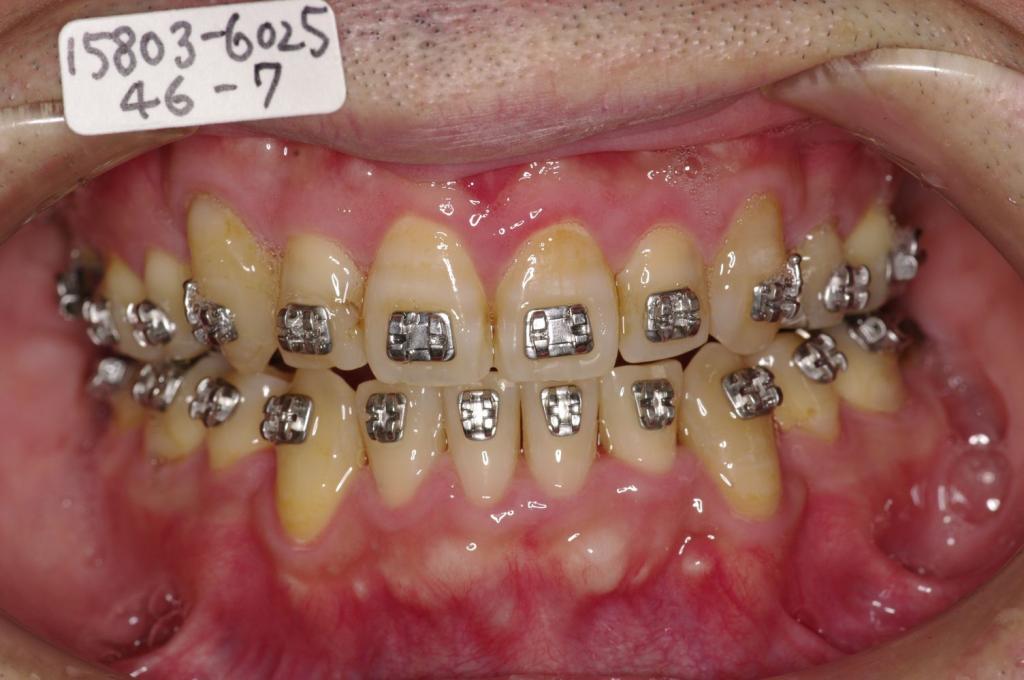

- 顎、顔の歪みの矯正治療

- 咬み合わせが悪い